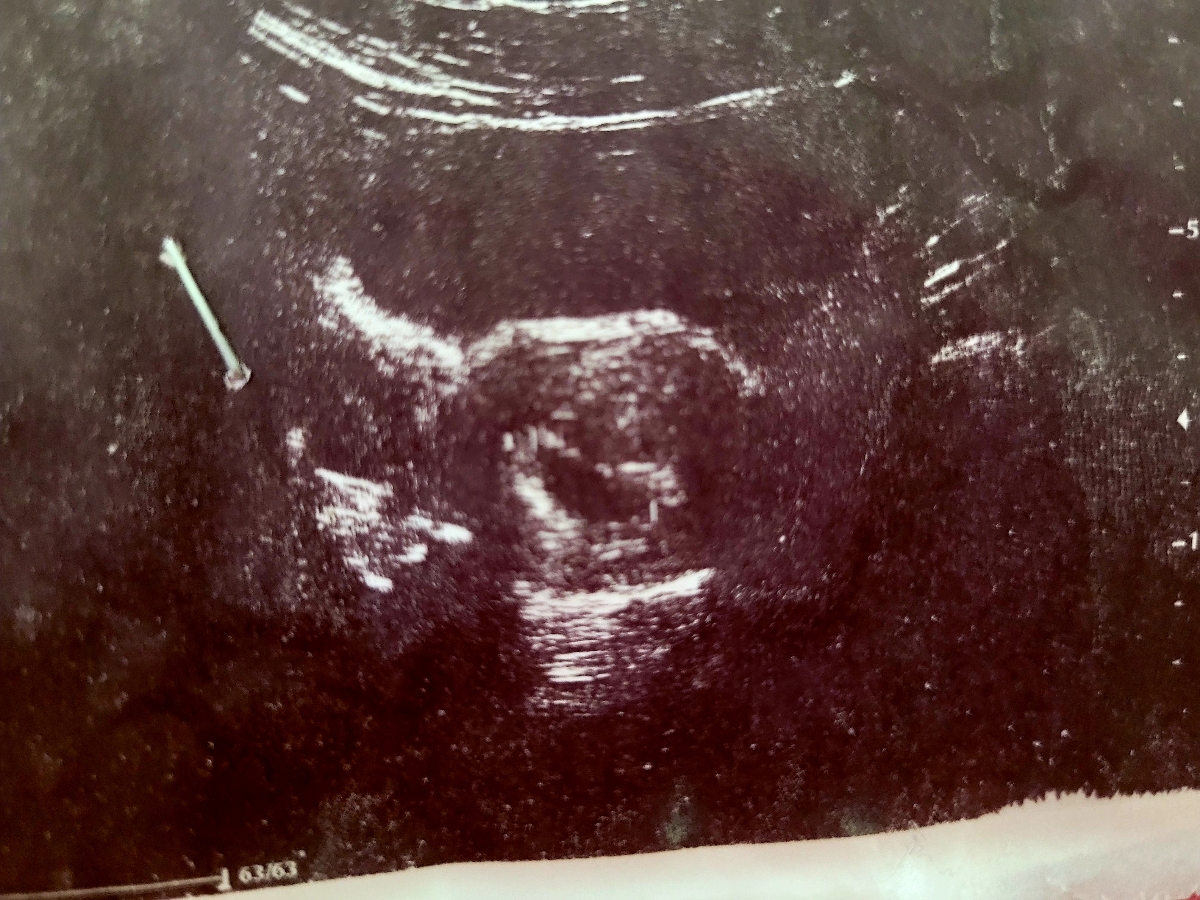

این عکس سونوگرافی هست دکتر

اینکه ساک حاملگی من نسبت به سن پریودیم بزرگ تره مشکلی نداره؟؟؟

۲۰ میلی متر هست

ساک بزرگ ک کیسه زرده دیده نشده مشکلی نداره؟؟؟؟؟

ساک بزرگ چون کیسه زرده نیست نشونه پوچ بودن که نیست؟؟؟

توی سونو دیروز نسبت به ساک سن حاملگی برام زده نسبت به GS ۶ هفته و ۲ روز هستم